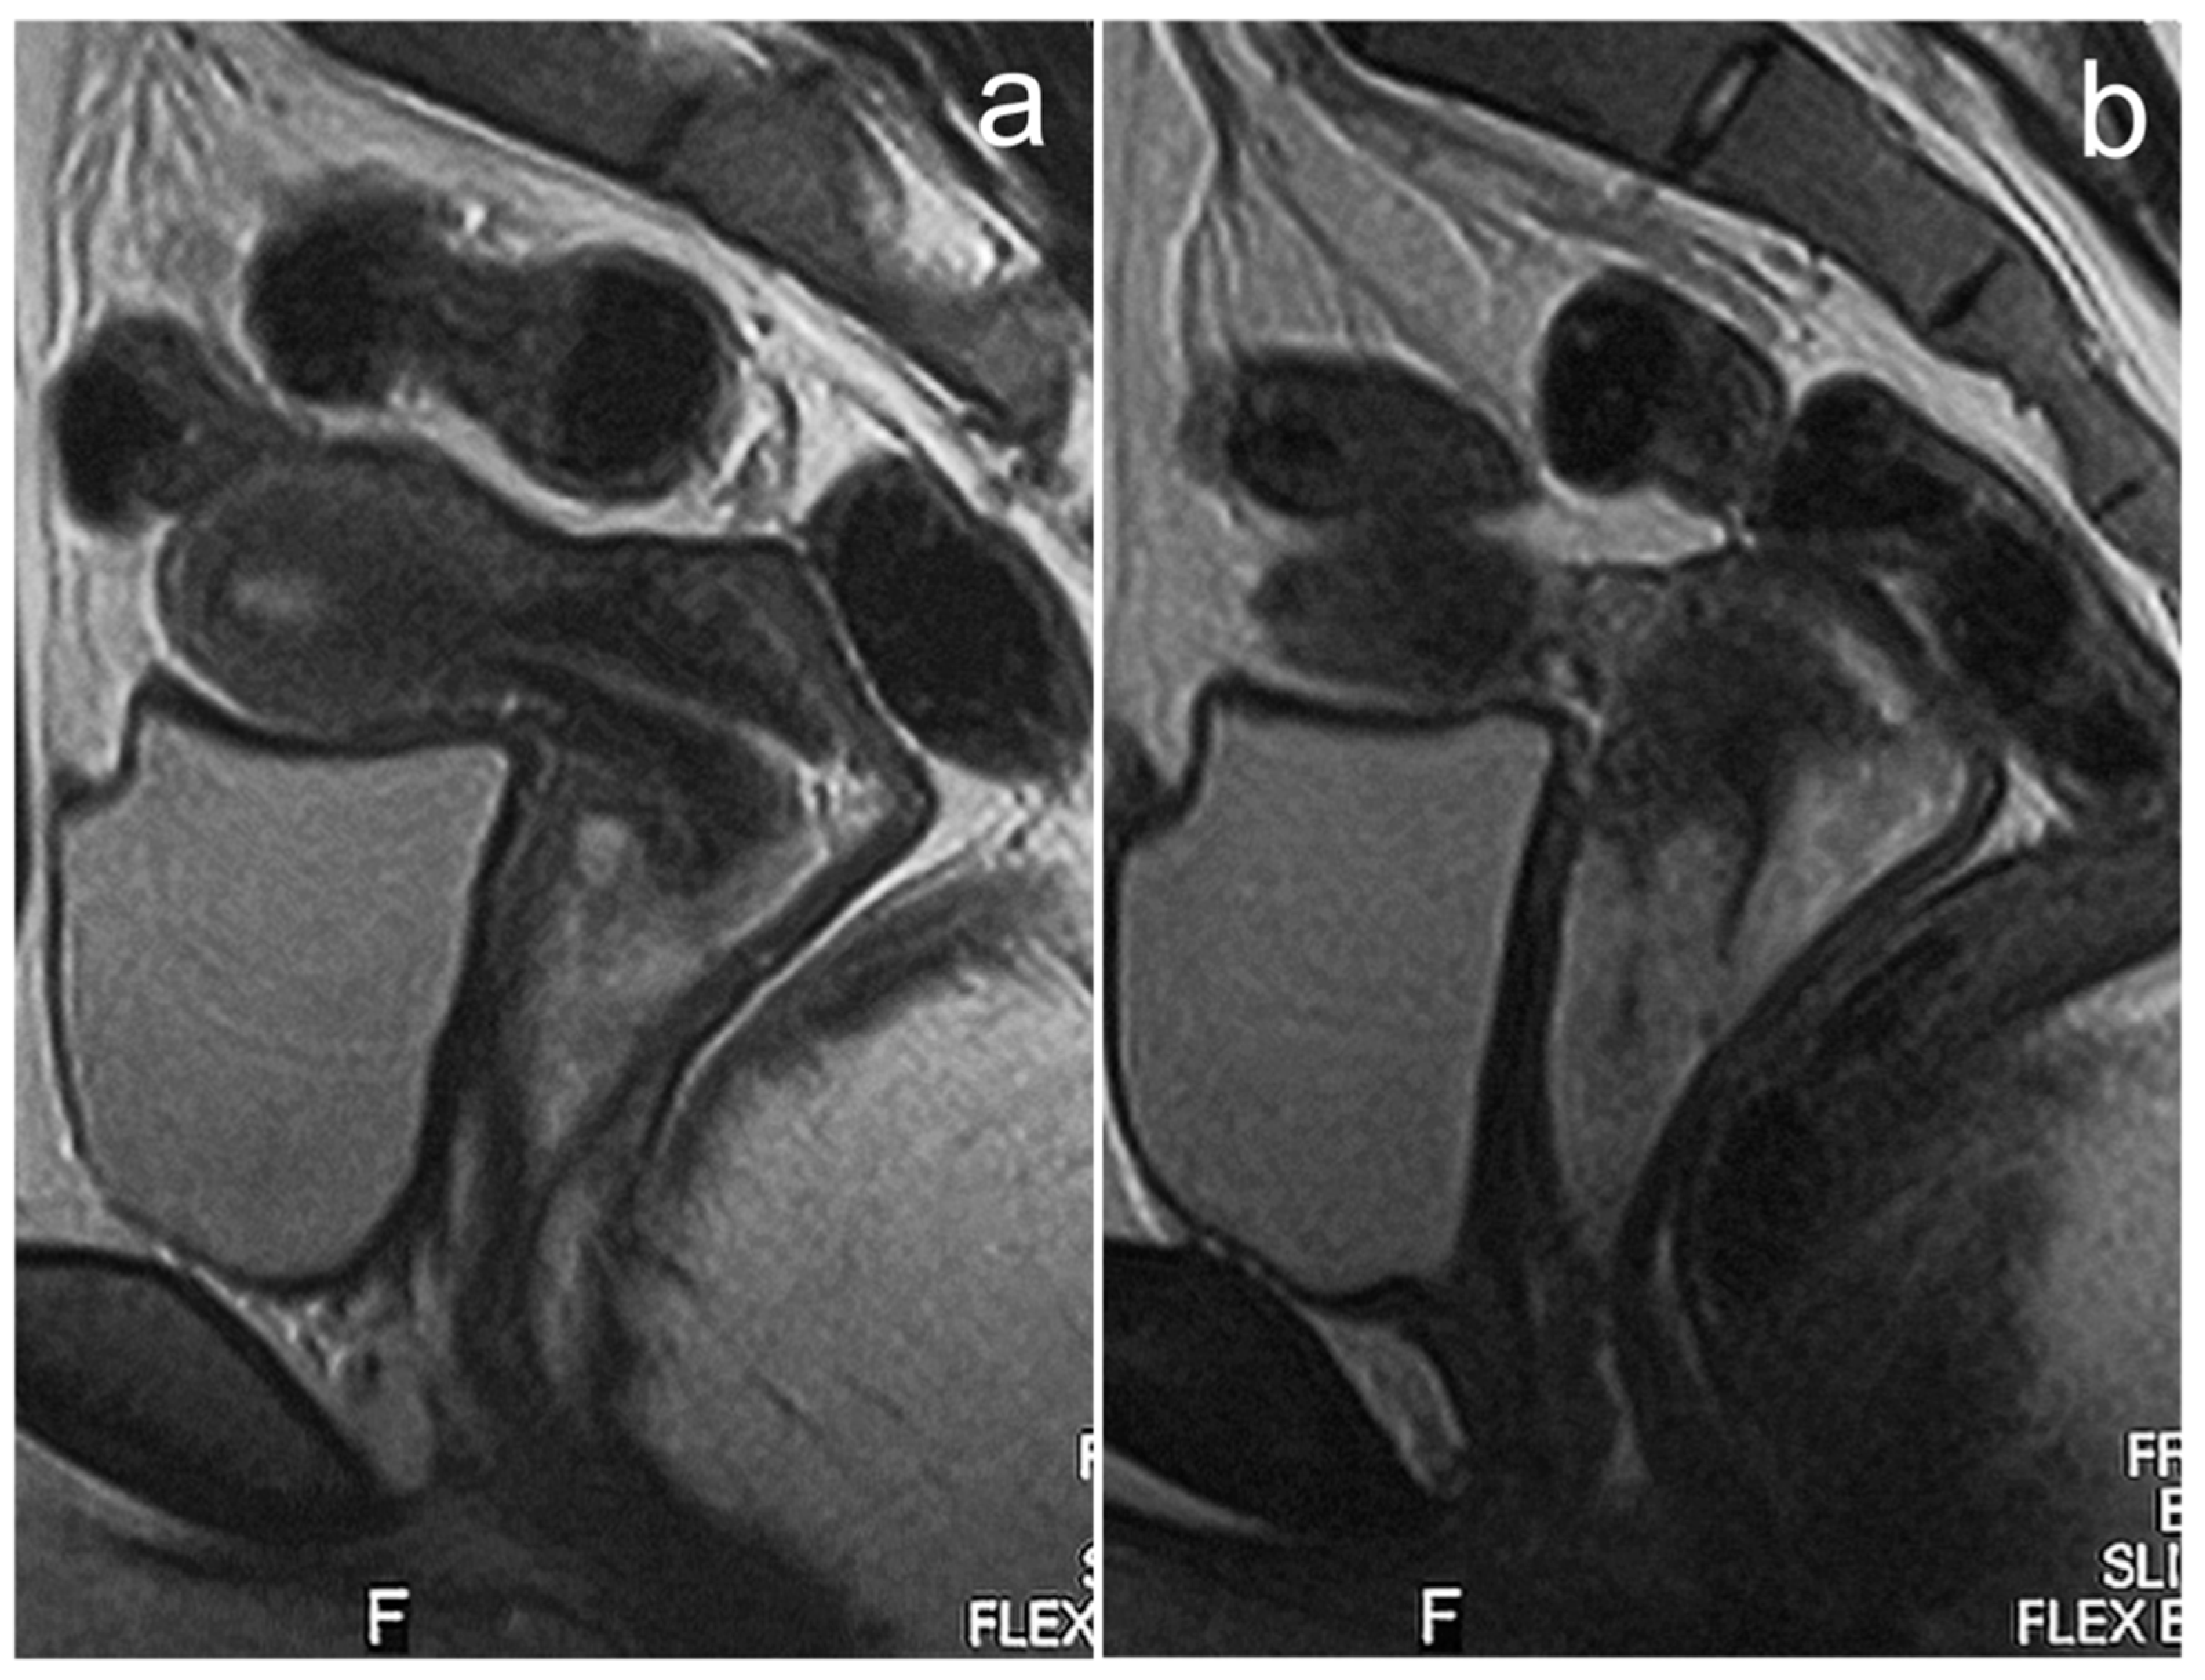

3.6. Cervical Cancer

| Cervical cancer | expansive or infiltrating mass; higher signal intensity than cervical stroma on T2WI, diffusion restriction | - | abnormal vaginal bleeding, vaginal discharge |